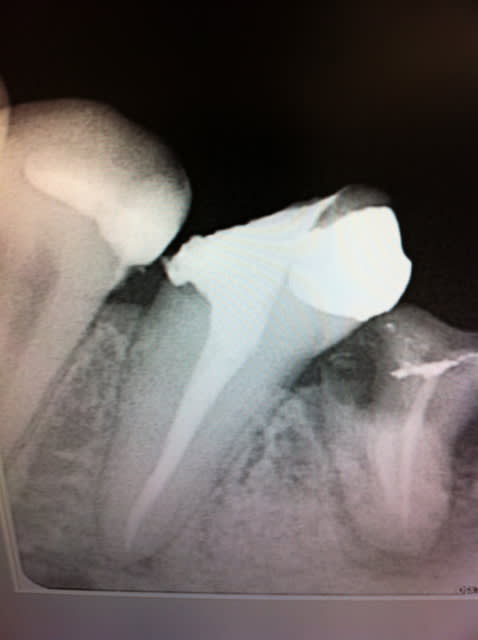

Patiente jeune, 23 ans, CMU, se présente au cabinet en urgence pour des douleurs très vives sur 46. Je diagnostique un abcès apical aiguë. J'ouvre, je draine, et rdv pour finir l'endo et couronner, et en même temps traiter la carie OD sur 45.

Disparition dans la nature. 6 mois plus tard, re-urgence. Voila le résultat.